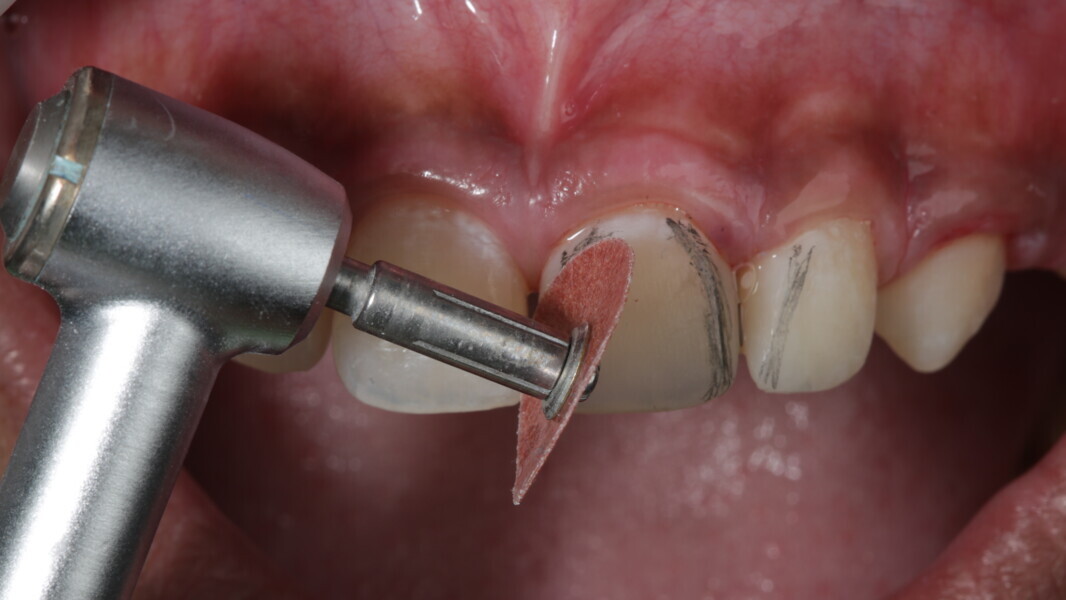

Fig 31-41: Polishing protocol and post-op

The article demonstrates how using the right protocols and armamentarium for composite materials can give life-like results in a short time in a minimally invasive way. No single layering technique can ensure a 100% success rate. Regardless of the technique, establishing good secondary and tertiary anatomy and thorough polishing are the key steps that make a restoration look more natural. Composite is the perfect material for allowing correction of mistakes or improvement.